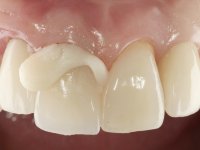

Primeira Fase.

O dente 1.1 foi preparado para uma coroa total, o afastamento gengival foi feito com caolino comprimido pela restauração provisória. A impressão foi feita com uma técnica de dupla mistura com dupla viscosidade. No laboratório foi confecionada uma coroa com infraestrutura em Zr revestida por cerâmica. A coroa foi cimentada em boca com cimento de ionómero de vidro reforçado por resina.